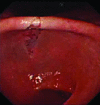

Figure 2

The tear involving the incisura.